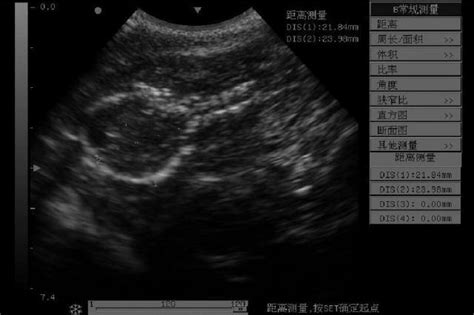

狗狗子宫蓄脓

狗狗子宫蓄脓,该怎么治?